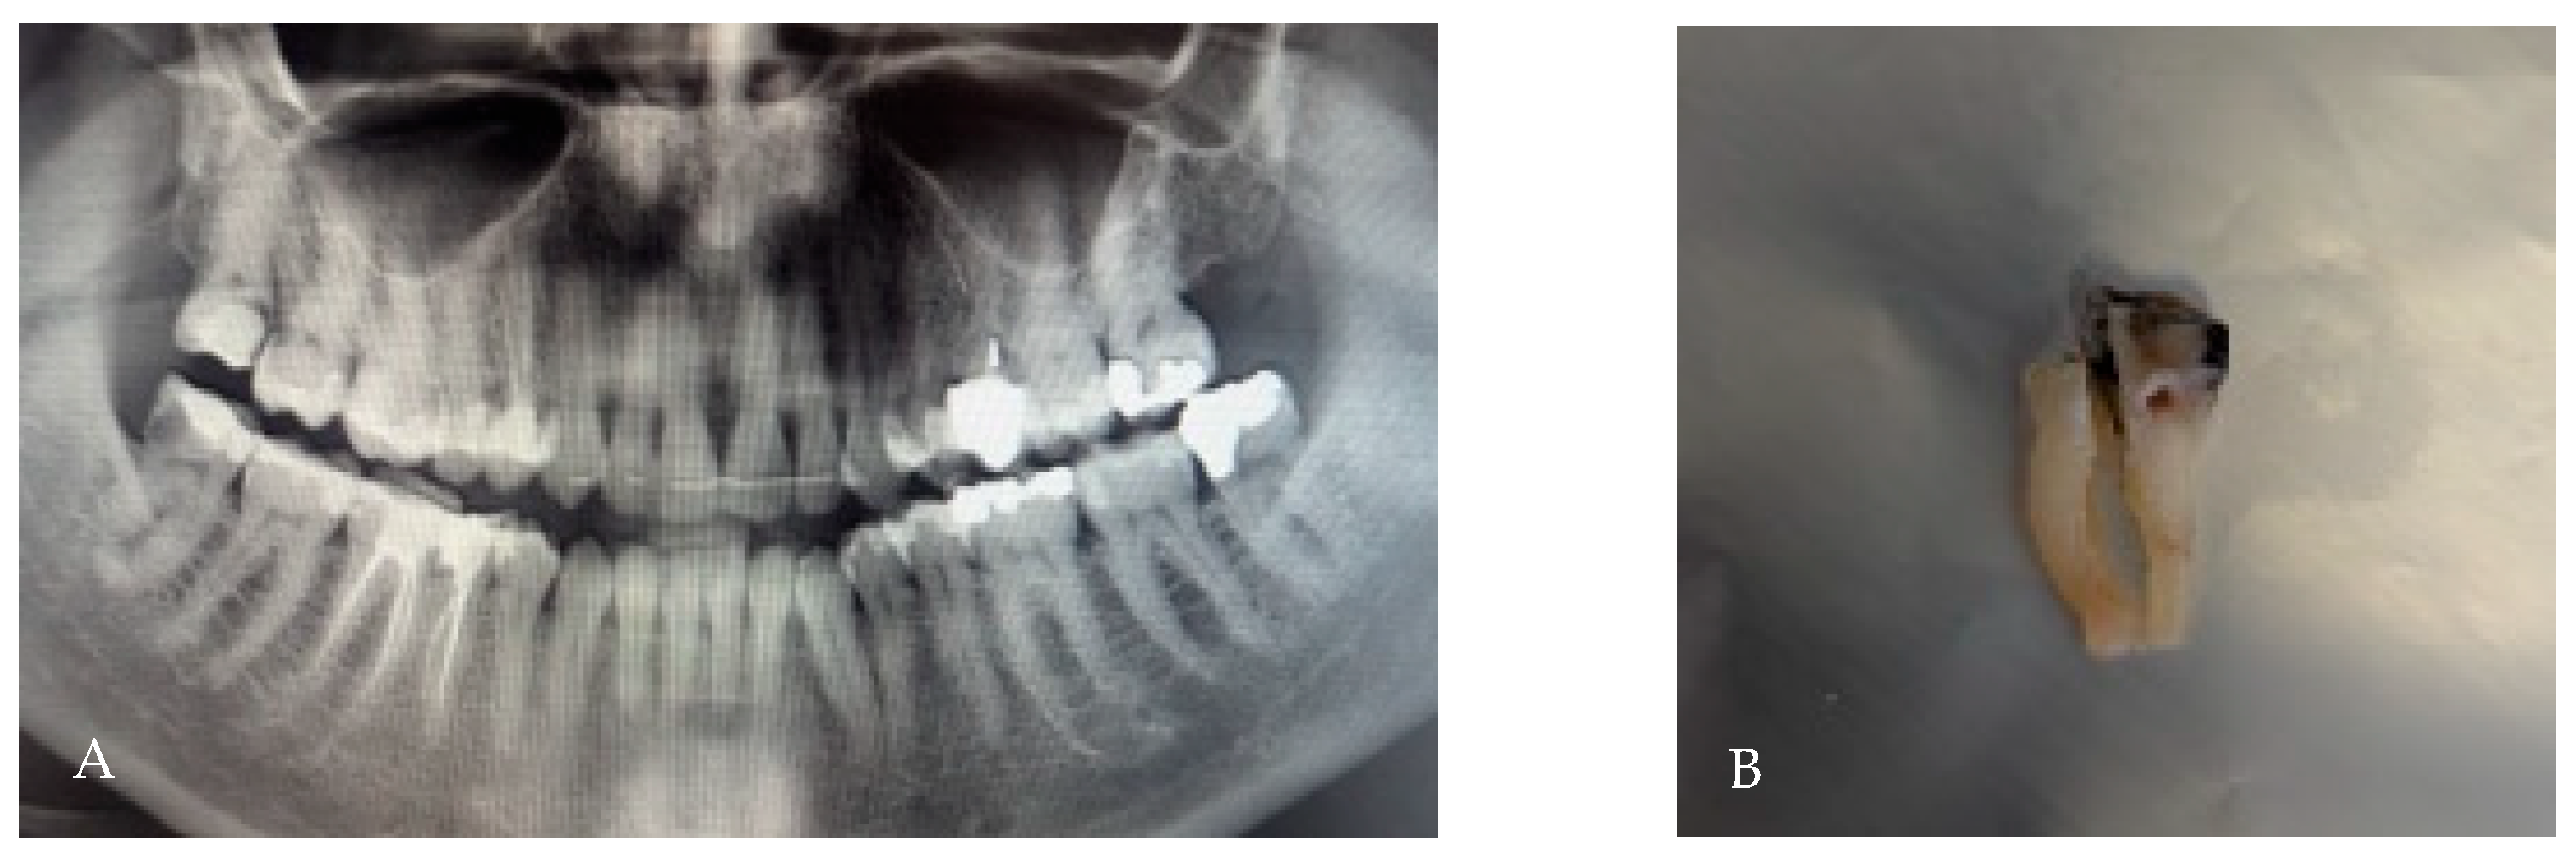

3.5. Root Fusion

3.6. C-Shaped Morphology

- C1: continuous C-shaped canal.

- C2: semicolon-shaped (due to discontinuation of the “C”).

- C3: two or more discrete canals without a clear C-shape.

- C4: single round or oval canal.